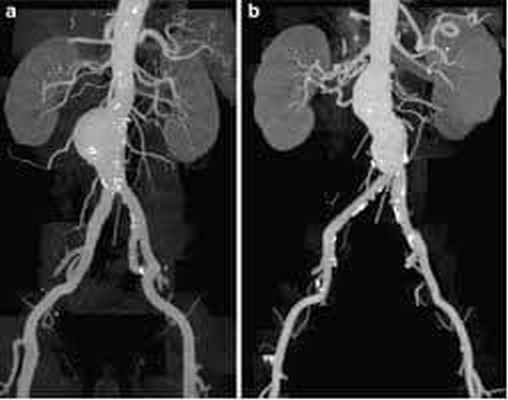

Наряду с традиционными операциями при аневризмах брюшной аорты, может быть применен новый метод лечения – эндопротезирование аорты. Метод заключается в том, что через небольшой прокол артерии на бедре, в аорту вводится длинная узкая трубка называемая катетером. Через катетер вводится специальный сосудистый протез, который изнутри фиксируется к нормальным отделам аорты выше и ниже месторасположения аневризмы.

Данный метод лечения является миниинвазивным, то есть гораздо легче переносится пациентом, короче период восстановления после операции – всего 2-3 дня. Однако его можно применить не во всех случаях.

Эндоваскулярное лечение аневризмы аорты с использованием имплантируемого стента является более безопасной альтернативой открытой операции. Эта процедура дает отличные результаты у пациентов с подходящим анатомическим строением.

Процедура проводится через небольшие разрезы в бедренных артериях. После пункции бедренной артерии проводник проводится через расширенную часть аорты, затем стент продвигается по проводнику. После правильного расположения стента, баллон расширяется, и стент раздвигает стенку сосуда, чтобы не допустить распространения аневризмы ниже почечных артерий.

Для гарантии надлежащей герметизации между имплантируемым стентом и аортой, большинство в настоящее время доступных стентов требует, чтобы у аневризмы проксимальный перешеек был по крайней мере на 1.0 - 1.5 см ниже почечных артерий. Однако, операция может быть сделана пациентам с аневризмами, у которых перешейки аневризмы короче или вообще отсутствуют, при помощи имплантации стента с многочисленными отверстиями и браншами к артериям почек или кишечника.

Эндопротезирование аорты

Более современный метод лечения аневризмы брюшной аорты, относящийся к гибридной хирургии. Данный метод сочетает в себе открытые хирургические технологии с эндоваскулярными, он представляет собой замену аневризматически расширенного участка аорты изнутри с использованием специального протеза, изготовленного в большинстве случаев «под заказ» (этим объясняется его высокая стоимость). Сосудистый протез специальным образом уложен в системе доставки. Его расправляют прямо в полости аневризмы, под контролем рентген-установки. Таким образом, протез исключает воздействие системного артериального кровотока на слабые растянутые стенки аорты.

Этот метод позволяет добиться результатов, сравнимых с открытой хирургической техникой, только с меньшим количеством осложнений, уменьшением сроков госпитализации и реабилитации пациента в 2 раза! Ограничивают применение этого современного метода только некоторые анатомические параметры самой аорты и высокая стоимость эндопротеза.